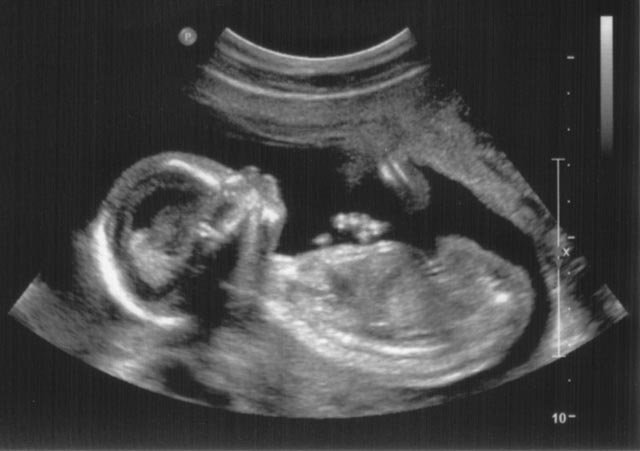

Pregnant women are often advised to continue taking prescribed medication for conditions like asthma, epilepsy, diabetes, or mental health, to keep themselves and their babies safe. From the very beginning, decisions about substances are shaped by advice, trust, relationships, and circumstances, not just by individual choice.

Some babies are born with Neonatal Abstinence Syndrome (NAS), meaning they may need extra care after birth because of substances they were exposed to during pregnancy, including some medicines their mother was prescribed and took in good faith. It’s a health issue that reflects how common medication and substance use already is, even before a child is born.